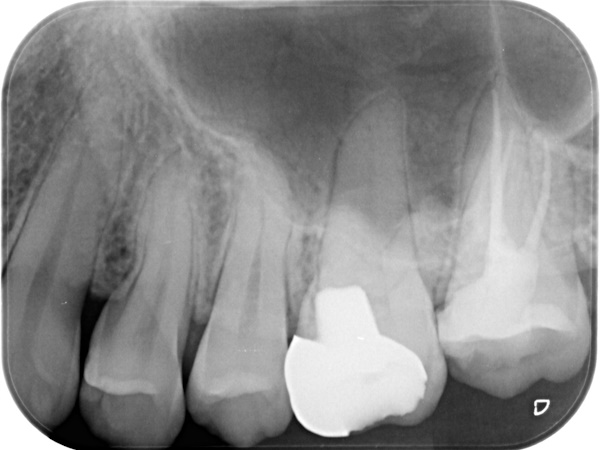

根管治療終了後3か月経過